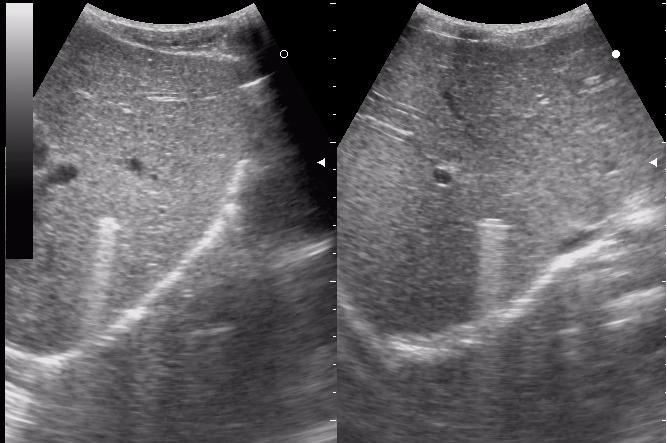

пуля из пневматического пистолета

+ на металле должен быть твинклинг артефакт